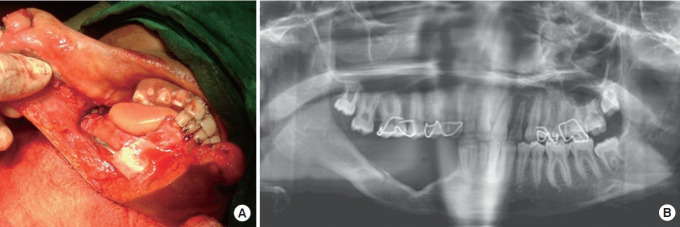

Background: Periosteum-mediated bone regeneration (PMBR) is a recognized method for mandibular reconstruction. Despite its unpredictable nature and the limited degree to which it is understood, it does not share the concerns of developmental changes to donor and recipient tissues that other treatment options do. The definitive role of the periosteum in bone regeneration in any mammal remains largely unexplored. The purpose of this study was to identify the genetic determinants of PMBR in mammals through a systematic review.

Results: A total of four studies satisfied the inclusion criteria. The subjects and tissues examined in these studies were Wistar rat calvaria in two studies, mini-pigs in one study, and calves and mice in one study. Three out of the four studies achieved the necessary quality score of ≥ 3. Gene expression analysis showed increased activity of genes responsible for angiogenesis, cytokine activities, and immune-inflammatory responses on day 7. Additionally, genes related to skeletal development and signaling pathways were upregulated on day 15. Conclusions: The results suggest that skeletal morphogenesis is regulated by genes associated with skeletal development, and the gene expression patterns of PMBR may be characterized by specific pathways.